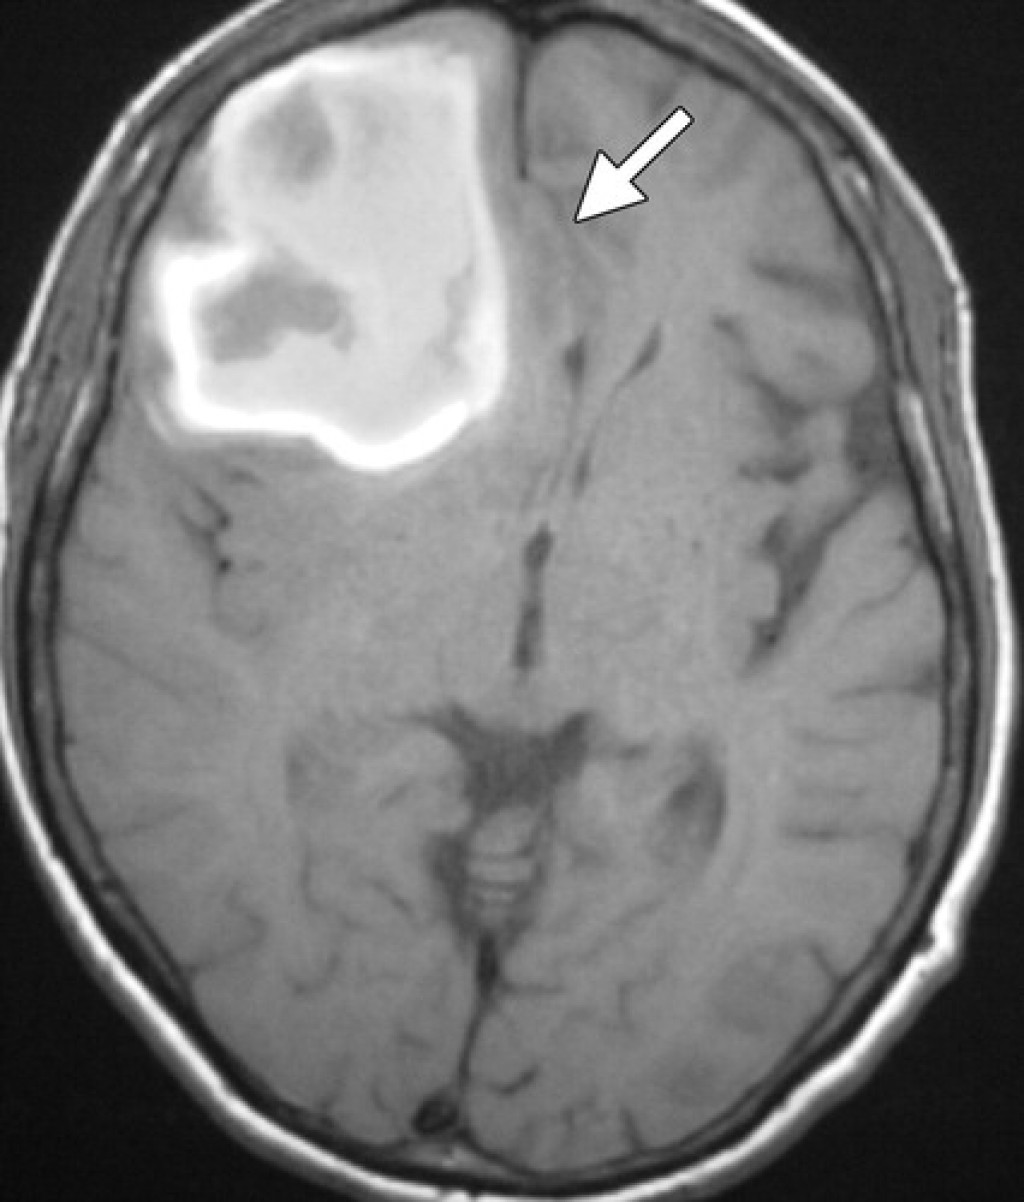

Медицинские аспекты и диагностика субдуральной гигромы мозга